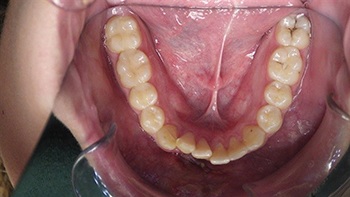

Figs. 7-8: Two-week follow-up with continued improvement in positioning and stabilization.

Over the following weeks, the orthodontic approach proved successful. Within a week, the extruded incisors showed visible improvement in position, and by two weeks, they were nearly realigned. The orthodontist planned to maintain the light archwire for several more weeks before replacing it with a bonded 3–3 retainer for long-term stabilization (Figs 3–8).

Throughout the short-term follow-up, the teeth remained firm and asymptomatic. The gingival and periodontal tissues appeared stable, with no signs of acute infection. Nevertheless, the community emphasized that this positive early response did not eliminate the need for long-term vigilance. Regular radiographs and ongoing monitoring by both the general dentist and an endodontist were considered essential.